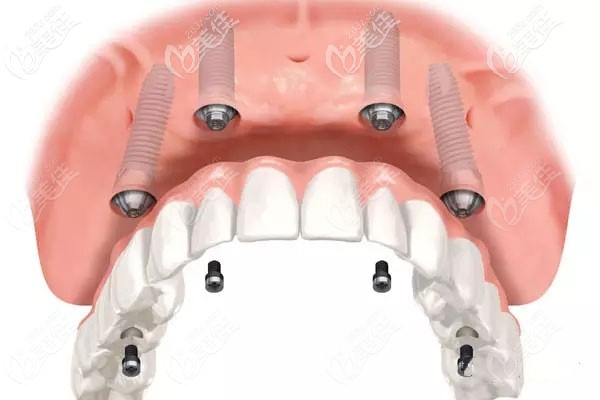

allon4,其實只是一種種植牙技術,就是用4顆種植體恢復半排牙齒,用8顆種植體就可恢復全口牙齒。而決定它價格的,主要是種植體的品牌。

該技術恢復半口牙只需要4顆種植體,還能減少植骨手術所產(chǎn)生的費用,另外,價格差異的主要原因在于你所選擇的種植體品牌,品牌不同收費就不同。